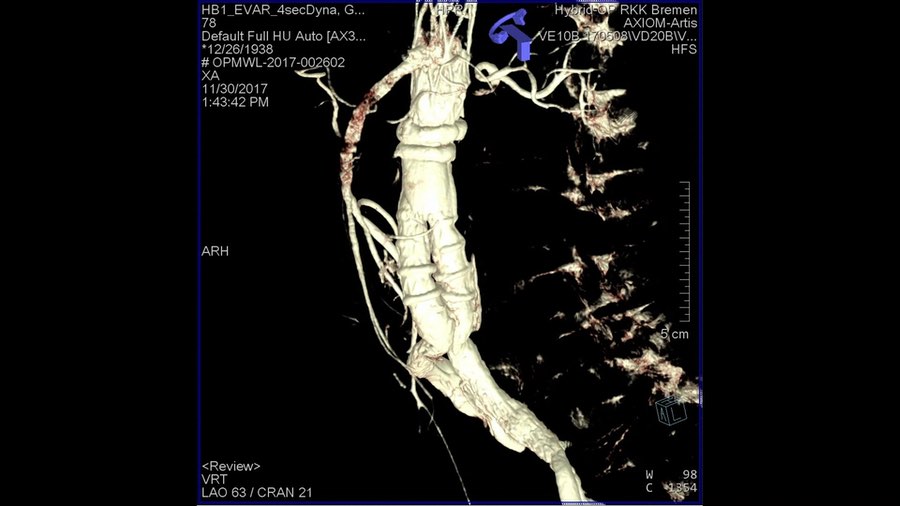

Prüfbericht des Medizinischen Dienstes (MD) bescheinigt dem größten Bremer Gefäßzentrum im Rotes Kreuz Krankenhaus Bremen (RKK) optimale Strukturen für die Behandlung von krankhaften Erweiterungen und Einrissen der Hauptschlagader (Aortenaneurysma)

Im Bereich der hochkomplexen Bauchschlagader (Bauchaorten)-Operationen fand im Sommer erstmals die Strukturprüfung des Medizinischen Dienstes (MD) im RKK- Gefäßzentrum statt. Denn damit ein Krankenhaus diese besonders schwierigen Eingriffe durchführen darf, muss es bestimmte Voraussetzungen erfüllen. Die Qualitäts- und Strukturprüfungen für bestimmte Behandlungen im Krankenhaus durch den Medizinischen Dienst sind bundesweit einheitlich geregelt und sehr streng. Die Gutachter beurteilen, ob die Qualität einer Untersuchung, einer Behandlung oder Pflegeleistung dem geforderten Qualitätsanspruch genügt. Die Vorgaben sind so streng, dass beispielsweise die Behandlung von Aorten in einigen Kliniken bundesweit zeitweise nicht mehr stattfinden durfte. Das Ergebnis des MD bescheinigt dem Gefäßzentrum des RKK jetzt nach der Prüfung, dass alle notwendigen qualitativen, strukturellen, medizintechnischen und personellen Ressourcen vorhanden sind – rund um die Uhr.

Für die optimale Behandlung von krankhaften Erweiterungen und Einrissen der Hauptschlagader (Aneurysmen) hatte das Rotes Kreuz Krankenhaus seine fächerübergreifenden Kompetenzen bereits 2019 in einem Aortenzentrum gebündelt. Es zählt zu den wenigen sogenannten high-volume centern, die in Deutschland mehr als 50 geplante Eingriffe bei erweiterten Schlagadern im Bauchraum pro Jahr durchführen.